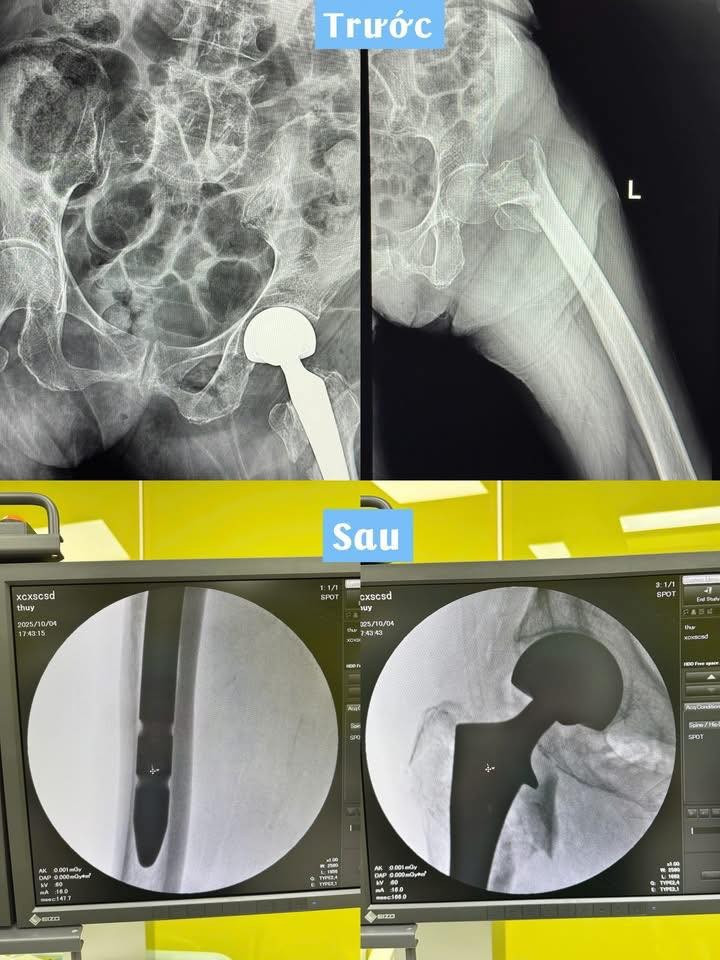

Hình ảnh xương đùi của bệnh nhân trước và sau phẫu thuật - Ảnh BVCC

Các bác sĩ Bệnh viện Đa khoa Khu vực Quảng Yên vừa phẫu thuật thành công ca thay khớp háng bán phần chuôi dài cho cụ bà 91 tuổi bị gãy liên mấu chuyển xương đùi trái – một trường hợp hiếm gặp, có nhiều yếu tố nguy cơ phức tạp do tuổi cao, sức yếu và mắc nhiều bệnh nền.

Các bác sĩ đã tiến hành thay khớp háng bán phần chuôi dài, một kỹ thuật đòi hỏi độ chính xác cao, đặc biệt ở người bệnh tuổi cao và có xương yếu.